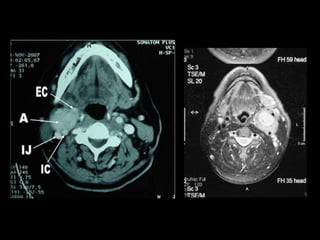

CT scan

• Locates tumor to prestyloid vs poststyloid

– Prestyloid tumor displace carotid artery posteriorly

– Poststyloid tumor displace carotid artery anteriorly

• Fat plane between mass and parotid

• Enhancement of lesion

– Schwannoma, paraganglioma, hemangioma,

hemangiopericytoma, aneurysm

• Limited soft tissue detail

MRI

• Most useful study

• Relationship of mass and carotid more easily

seen than with CT